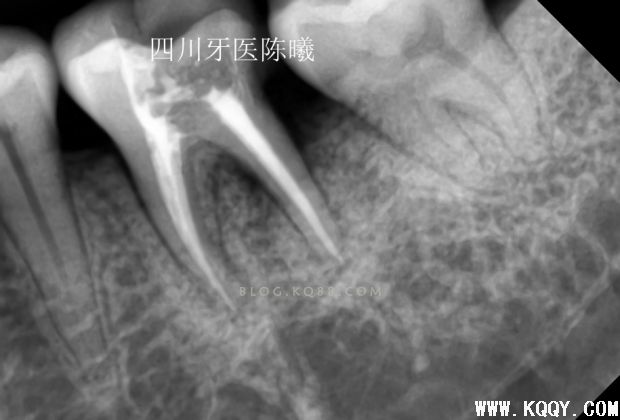

这次留个后路,把刚才超填的牙胶去掉头部1MM,然后保留大部分牙胶,紧密充填后拍片!,终于感觉及格了,还是多角度看看

进一步确定感觉没有大问题了,终于可以告诉患者根充结束了,由于反复操作,时间过长,担心出问题,病人也在考虑要不要做修复体,所以最后暂封上部观察